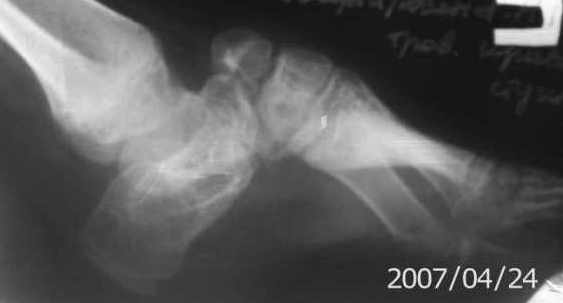

Здравствуйте, уважаемые коллеги. Ребенок 8 лет с диагнозом Артрогрипоз состояние после операции на правой стопе,рецидив(операция по Зацепину).

Девочку оперировали в возросте 1 год в другом городе.На данный момент стопа деформирована,отмечается эквино-поло-варусная деформация правой стопы.Посоветуйте пожалуйста тактику лечения.С уважением Игорь.

That looks like calcaneo-cavus, not equino varus

Полагаю, что больной показана коррекция деформации пяточной кости по Илизарову; "трехсуставной" (кавычки - с учетом измененной анатомии) артодез с последующей коррекцией остаточной деформации (если не удастся устранить 100% одномоментно при артродезе) и укорочения стопы по Илизарову.

Уважаемый Игорь, эффективно устранить эквино- варусную деформацию стопы в данном случае возмжно только при вмешательстве на скелете стопы, трёхсуставной артродез с коррекцией положения стопы,остеосинтез АИ.

Обычно такие вмешательства практикуются начиная с 9 лет. Основной минус - нарушение роста стопы. Закрытая аппаратная коррекция возможна, но требует опыта и чревата фиброзным анкилозированим суставов стопы и деф. артрозом в перспективе.